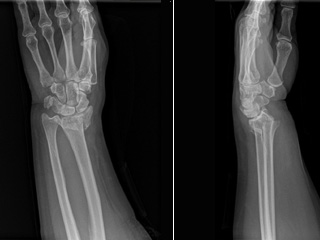

Clínicamente el paciente acude a hospital con dolor severo con deformidad e impotencia funcional de la muñeca y tras ser evaluado por el equipo médico se completa el estudio de imagen mediante radiografías antero posterior y lateral que serán evaluadas por el cirujano ortopédico que tomara la decisión de tratamiento definitivo según el tipo de lesión.